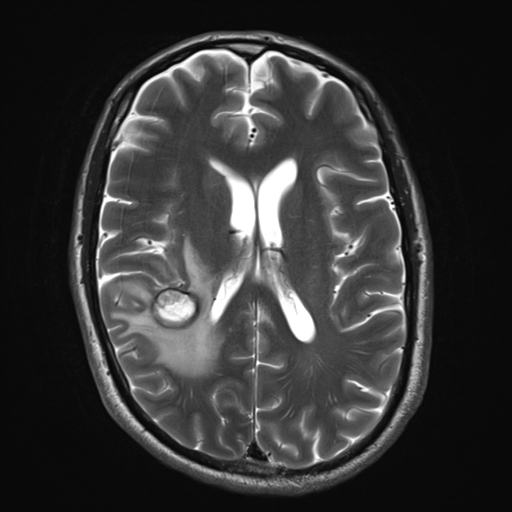

Изображения и частично текст взяли с радиопедии radiopaedia.org. 1 МРТ Т1, 2 МРТ Т2 (кейс 1), 3 - КТ с контрастом (кейс 2)

Это разделение критически важно для лучевой диагностики. Исследование Isiklar (1995 г.) показало, что характерные признаки МРТ (гиперинтенсивный сигнал на T1 и гипоинтенсивный на T2) сигнал наблюдается только у меланотических метастазов. К сожалению, на их долю приходится лишь около 25% случаев, в то время как амеланотические метастазы имеют неспецифическую картину.

Магнитно-резонансная томография (МРТ)

Ключевой особенностью является высокая частота спонтанных кровоизлияний, что делает меланому одним из самых геморрагичных метастазов наряду с хориокарциномой.

Это приводит к сходной картине: гиперинтенсивный сигнал на T1-ВИ и гипоинтенсивный на T2-ВИ.

Ключевые МР-признаки:

T2-ВИ: Часто гипоинтенсивный.

*T2 (GRE) / SWI:** Важный диагностический признак. Выраженные артефакты магнитной восприимчивости (гипоинтенсивный "ободок") связаны в первую очередь с геморрагическим компонентом (гемосидерин), а не с меланином, который обладает слабым диамагнитным эффектом.

Артефакты восприимчивости встречаются в 42% случаев метастазов меланомы (для сравнения, при метастазах рака легкого — лишь в 8%).

Некоторые мелкие метастазы могут быть видны только на T2*/SWI, однако интерпретировать изолированные гипоинтенсивные очаги на этих последовательностях следует с осторожностью.